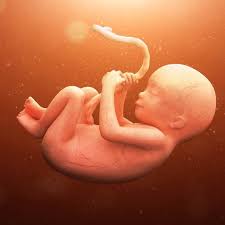

مراحل النمو و التطورات التي تطرأ على الأم و الجنين في الشهر السادس من الحمل كبسولة

جنينك في الشهر السادس سوبر ماما

الشهر السادس من الحمل و تطورات الجنين و نصائح هامة للحفاظ عليه